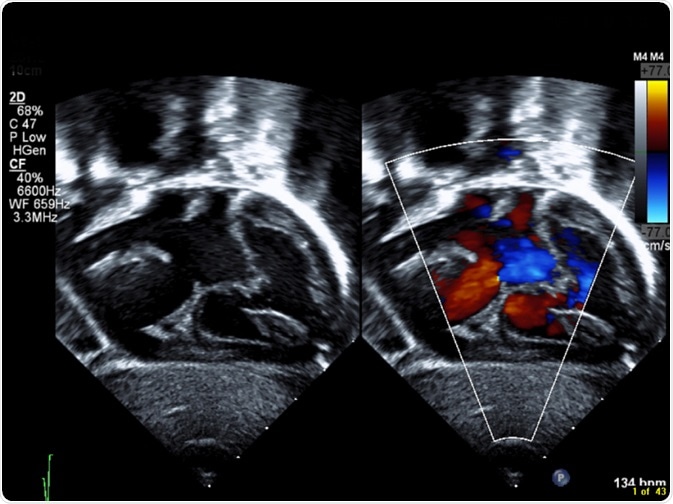

Septal defects are colloquially known as “holes” in the heart. These arise when there are abnormal connections between any of the heart’s chambers, which normally only communicate via a system of valves that open and close with contraction of the heart.

Similarly, there may be narrowing between the right ventricle and the pulmonary artery, known as pulmonary stenosis. This makes it significantly harder for the heart to pump blood to the lungs and results in increased strain on the heart, which in turn may present with some of the abovementioned signs and symptoms.

Transposition of the great arteries, although rare, is a serious condition. There is swapping between the two main blood vessels (i.e. the pulmonary artery and the aorta) that exit the heart. When this occurs, there is no longer the physiological flow of blood from the pulmonary artery to the lungs to collect oxygen that is later sent to the rest of the body from the heart via the aorta.

Instead, blood flows to the lungs and picks up oxygen, but that oxygenated blood is pumped back into the heart ultimately as opposed to being pumped to the rest of the body.